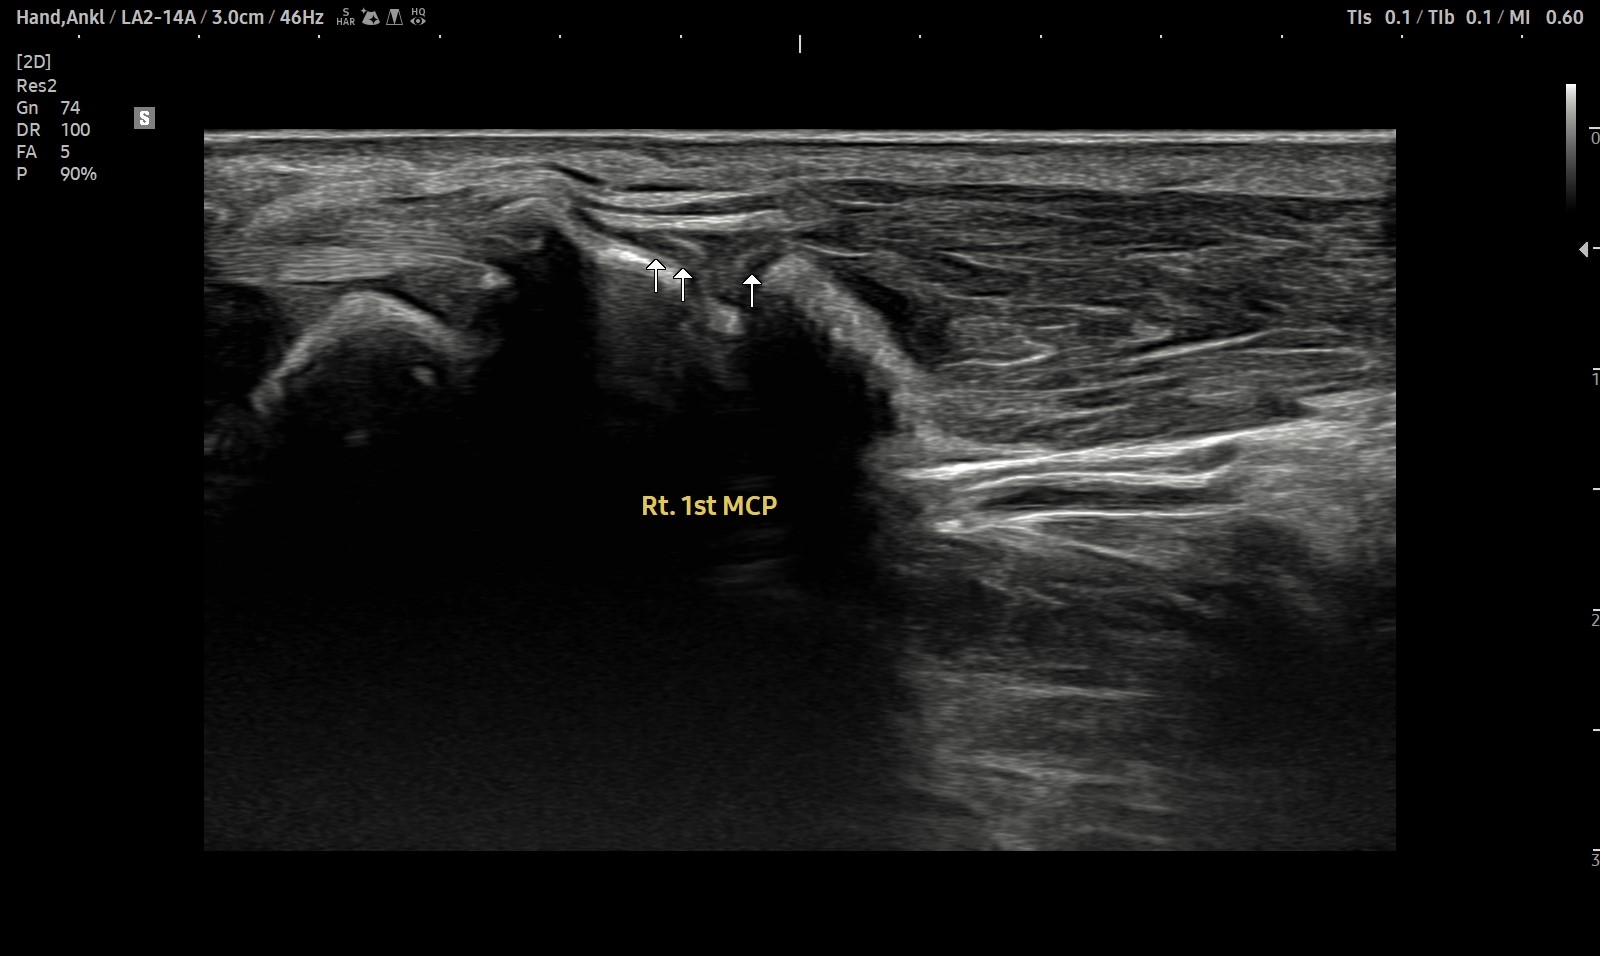

- 치료기간 : 25 . 5 . 7 ~ 25 . 8 .12

- 치료횟수 : 4cycle(20) 회

치료전

치료후